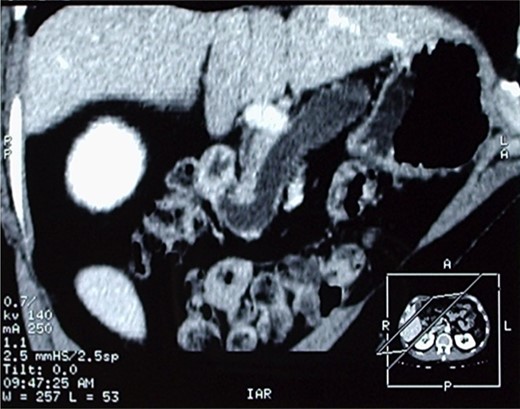

The patient therefore underwent a computed tomography (CT) scan (Figs 1 and 2) that revealed ‘a thickened duodenal wall and a sero-cystic lesion of the pancreatic head without contrast-enhancement, which compressed the duodenal lumen and caused a dilation of the Wirsung duct’. The liver, the gallbladder and the extrahepatic biliary tree were normal. No lymphadenopathy was found.

CT-scan, showing a sero-cystic lesion of the pancreatic head without contrast-enhancement, compressing the duodenal lumen and causing a dilation of the Wirsung duct.